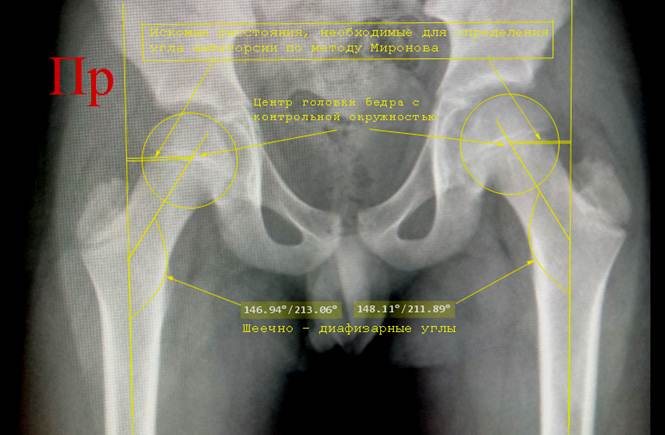

Снимок

таза ребенка 11 лет. Начерчены шеечно – диафизарные углы, отмечены центры

головок бедер. Выполнена проверка центров окружностями. Выполнено дальнейшее расчерчивание для

определения показателей, необходимых для

определения геометрии проксимального

отдела бедра по методу Миронова.